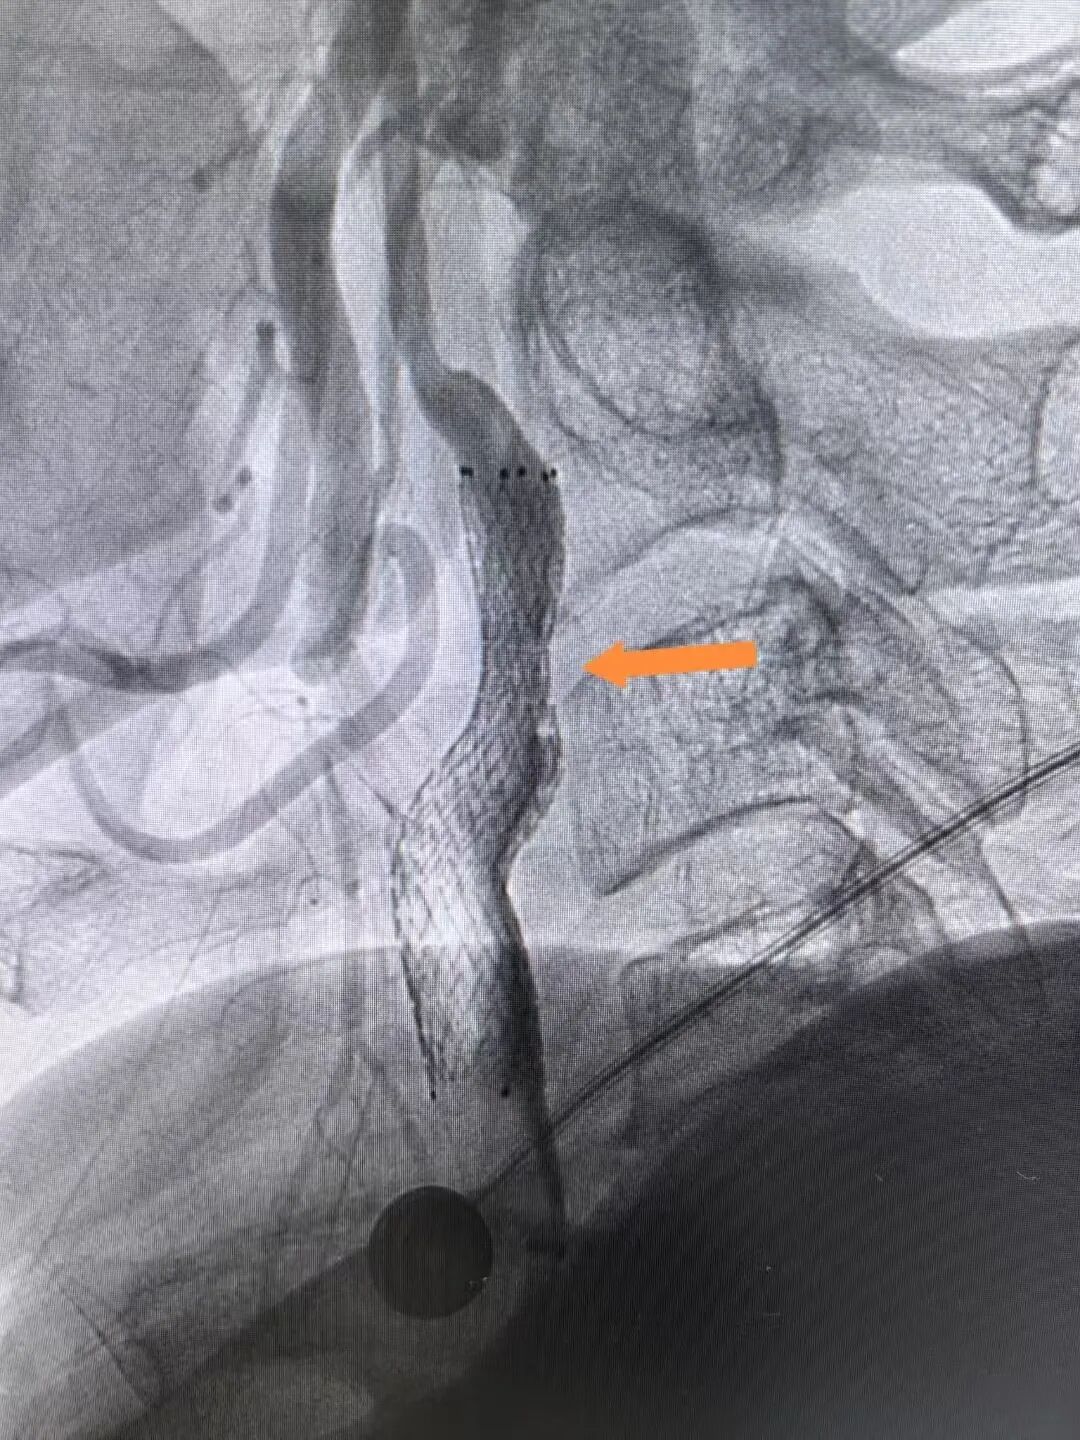

2025年3月4日手术当天,医生穿刺患者右桡动脉进行造影时,一场危象毫无征兆地出现:患者前降支血管近段狭窄达99%,血管近乎完全闭塞。这意味着心脏随时面临因严重缺血而停跳的危险,大脑也承受着巨大且不可逆的缺血性损伤风险,情况刻不容缓,必须立即进行紧急手术,这是挽救患者生命的关键。

冠脉造影显示患者前降支血管重度狭窄

支架植入后,患者前降支血管血流恢复通畅